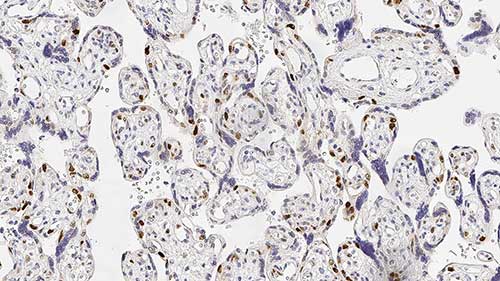

Human placenta: immunohistochemical staining for p57 protein. Note nuclear staining for cytotrophoblast and stromal cells of the villi. p57: clone 25B2

Es besteht zunehmend Interesse an p57 als Marker bei Gestationserkrankungen. Der Begriff Keimstrang-Stromaerkrankung bezieht sich auf ein breites Spektrum an proliferativen Störungen der Plazentatrophoblasten mit einer Vielzahl an histologischen Erscheinungsbildern und klinischen Verhaltensweisen.